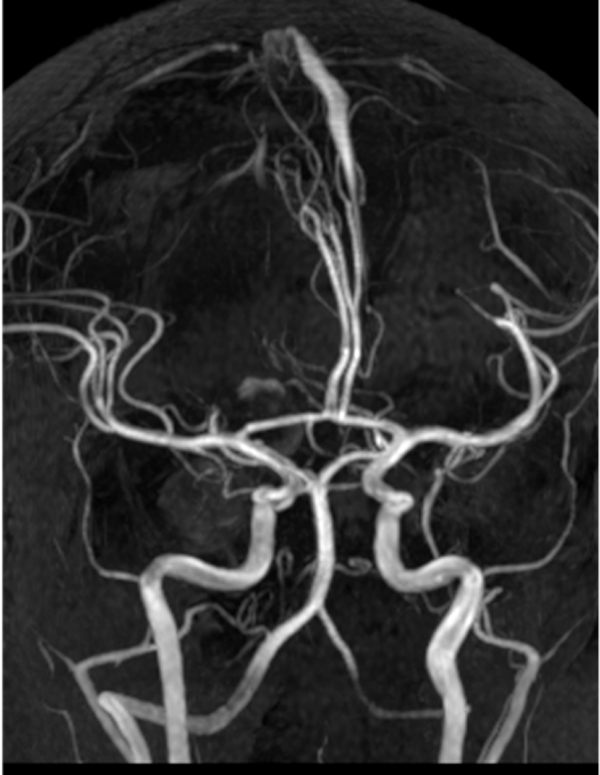

Figura 2. AngioRM de vasos intracraneales. Control posterior a la embolización aneurismática, sin evidencia de aneurismas residuales.

Dos años más tarde, en control por Infectología, refirió cefalea holocraneana pulsátil de moderada intensidad, asociada a mareos, náuseas y vómitos esporádicos. Se solicitó una nueva angioRM, la que arrojó un aneurisma fusiforme de la arteria comunicante anterior con compromiso del segmento A2 izquierdo e irregularidad asociada de M1 derecho (Figuras 3 y 4). Ante estos hallazgos se efectuó angiografía cerebral con colocación de un diversor de flujo, angioplastia con balón y embolización con “coils”.